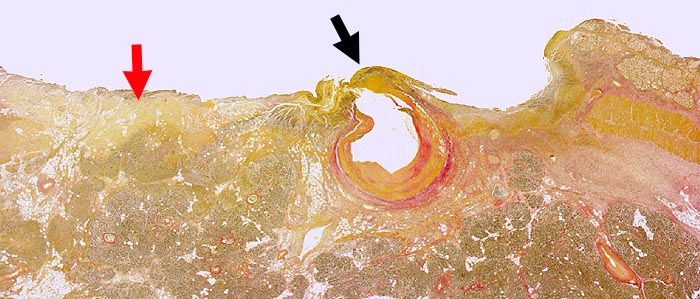

Chronisches Ulkus duodeni: Arrosion A. pancreaticoduodenalis

Bis in das Pankreas penetrierendes Duodenalulkus. Im Zentrum die arrodierte Arteria pancreaticoduodenalis.

Tödliche Ulkusblutung bei Gefässarrosion. NSAR Medikation.